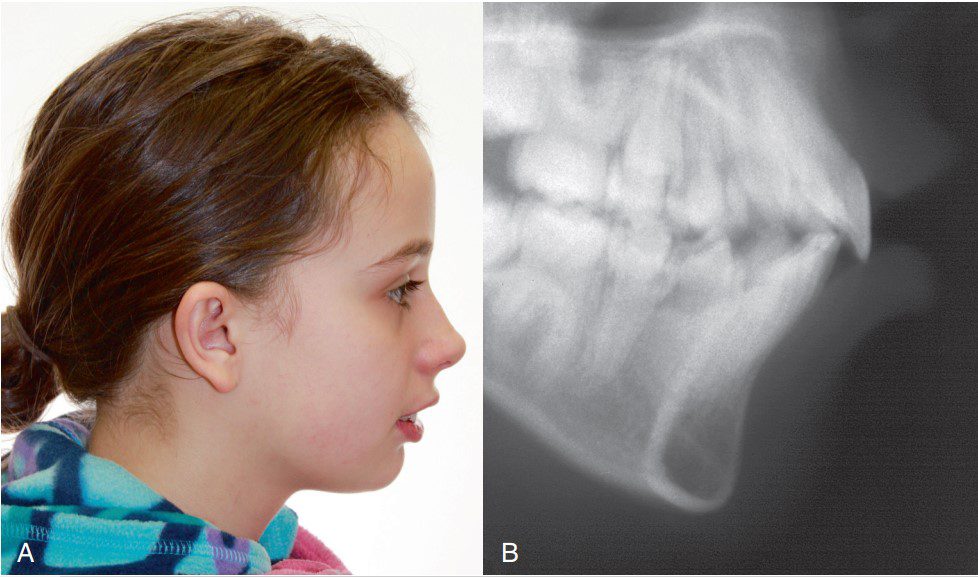

Để đánh giá vị trí của hàm trên và hàm dưới trong quá trình khám lâm sàng, cần xác định một mặt phẳng tham chiếu phù hợp. Trong thực hành lâm sàng, đánh giá dễ dàng nhất có thể được thực hiện bằng tư thế đầu tự nhiên, thường sử dụng khi chụp ảnh ngoài mặt. Phân tích chi tiết hơn về tương quan mô mềm theo chiều trước – sau sẽ được thực hiện trên phim sọ nghiêng.

Thông thường, tương quan song song hoặc có góc âm nhẹ (điểm cổ họng nằm cao hơn điểm menton) được thấy ở những khuôn mặt có thẩm mỹ tốt (hình 1-27A). Cằm kém phát triển sẽ thể hiện qua sự giảm chiều dài từ cằm đến cổ họng (hình 1-27B).

Phân tích chiều đứng không chỉ giới hạn ở phần trước của khuôn mặt mà còn bao gồm cả phần sau. Tỷ lệ bình thường giữa tầng mặt dưới và tầng mặt sau là 0,69. Đánh giá tổng thể tương quan này có thể được thực hiện thông qua mặt phẳng hàm dưới. Việc sờ nắn và đặt một vật phẳng dọc theo bờ dưới của xương hàm dưới có thể giúp hình dung tương đối độ nghiêng của mặt phẳng này.

Trong phân tích chiều đứng từ góc nhìn nghiêng, khuôn mặt thường được phân loại là hội tụ (mặt ngắn) hoặc phân kỳ (mặt dài).

- Ngược lại, mặt dài được đặc trưng bởi tầng mặt trước tăng lên rõ rệt so với mặt sau, góc mặt phẳng hàm dưới dốc, có thể có tình trạng môi không khép kín với khoảng hở liên môi lớn, rãnh môi–cằm nông (hình 1-29B).